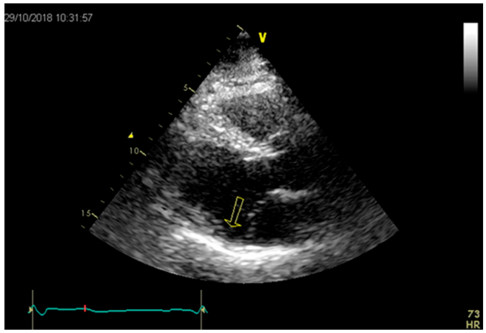

Veamos la siguiente imagen (Figura 4): es un ejemplo característico de la disyunción del anillo según la definición de que solo es posible verla en sístole. La flecha marca una zona amplia de separación entre la posible inserción de la válvula y la unión auriculoventricular.